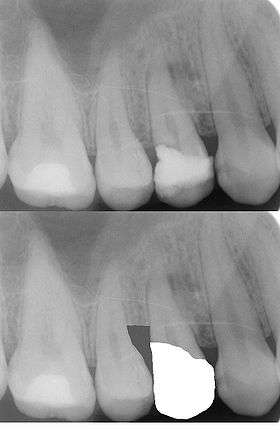

An alternative to surgical crown lengthening is orthodontic forced eruption, it is non-invasive, does not remove or damage the bone and can be cost effective. The tooth is extruded a couple of millimeters with simple bracketing of adjacent teeth and using light forces this will only take a couple of months. A fiberotomy is performed after crown lengthening and is easily performed by the general dentist. In many cases such as this one shown, surgery and extraction may be avoided if patient is treated orthodontically rather than periodontally.